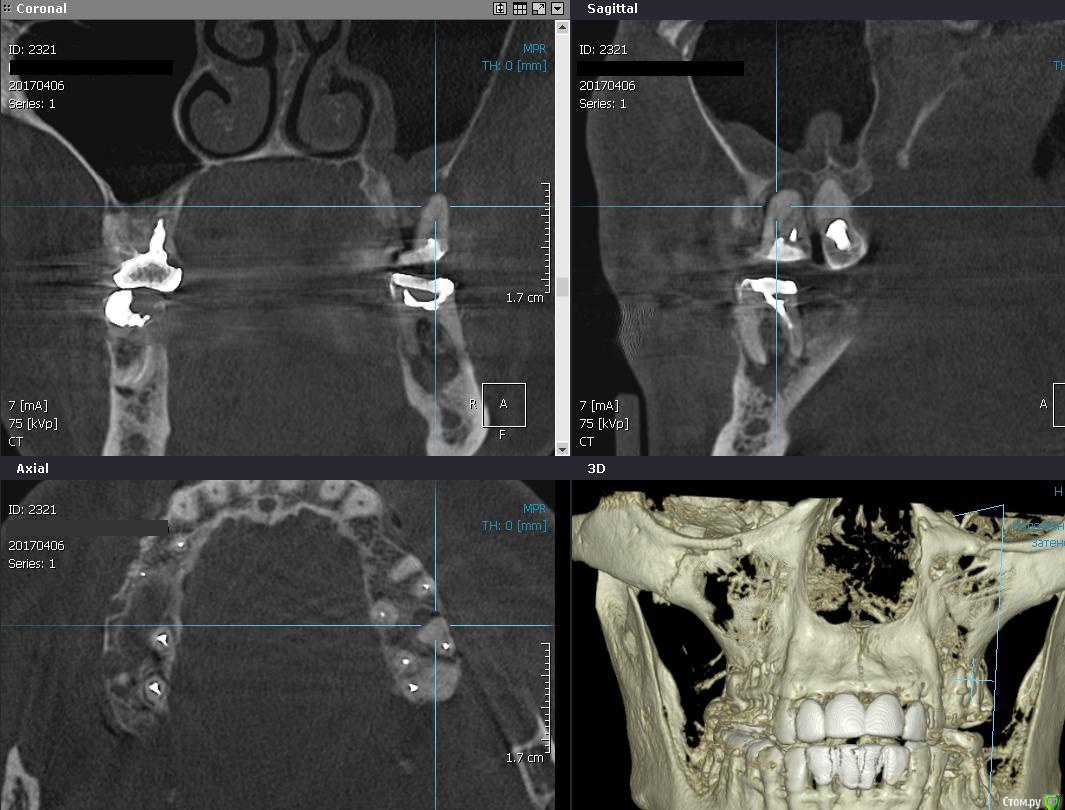

gum Опубликовано 10 апреля, 2017 Поделиться Опубликовано 10 апреля, 2017 Я за удалить и отпустить на пару месяцев и еще 36 похоже тоже удалить.Повторное КТ и уже планировать далее. 1 Ссылка на комментарий

Bier Опубликовано 10 апреля, 2017 Поделиться Опубликовано 10 апреля, 2017 все ок тут в пазухе. Не трогайте. Удалите, подождите, спокойно делайте синуслифт. 1 Ссылка на комментарий

колесников Опубликовано 10 апреля, 2017 Поделиться Опубликовано 10 апреля, 2017 Удаление с консервацией 1 Ссылка на комментарий

Irouil Опубликовано 10 апреля, 2017 Поделиться Опубликовано 10 апреля, 2017 Удаление с консервацией+1Может без синуса даже выйдет Ссылка на комментарий